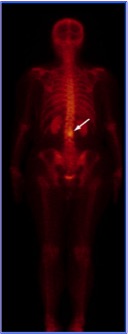

Types of tests: planar bone scintigraphy, SPECT/CT of the skeleton.

Aim: to visualize abnormalities of the skeleton (local areas of metabolic dysfunction of bone tissue).

Imaging agent: Tc-99m-labeled phosphate complexes. Tc-99m-labeled bisphosphonates The mechanism of visualization of metastases involves the inclusion of the imaging agent into the mineral metabolism of the bone tissue and its active storage in the areas of increased bone formation (mineralization), accompanying bone destruction process.

Principles: 2-3 hours after an intravenous injection of the imaging agent, a full body bone scan is made.

Nuances: bone scintigraphy is a high-sensitivity / low specificity test. In some instances, osteochondrosis, arthrosis and changes of the skeleton caused by trauma may lead to an erroneous conclusion. In this case, it is recommended to perform SPECT/CT. The use of Tc-99m-labeled bisphosphonates increases the sensitivity of the test.

SPECT/CT of the skeleton allows a better assessment of the condition of the skeleton if the results of bone scintigraphy are inconclusive. It helps to identify metastases that are 5-10 mm in size. It is a reliable technique for evaluating the efficacy of treatment of metastases with bisphosphonates and chemotherapeutic agents. SPECT/CT is recommended for patients with primary cancer of the prostate and breast, kidney and urinary bladder cancer, lung cancer (if PET/CT cannot be performed), melanoma, histiocytosis, malignant neoplasms of the gastrointestinal tract and reproductive system, embryonal tumor and osteosarcoma.